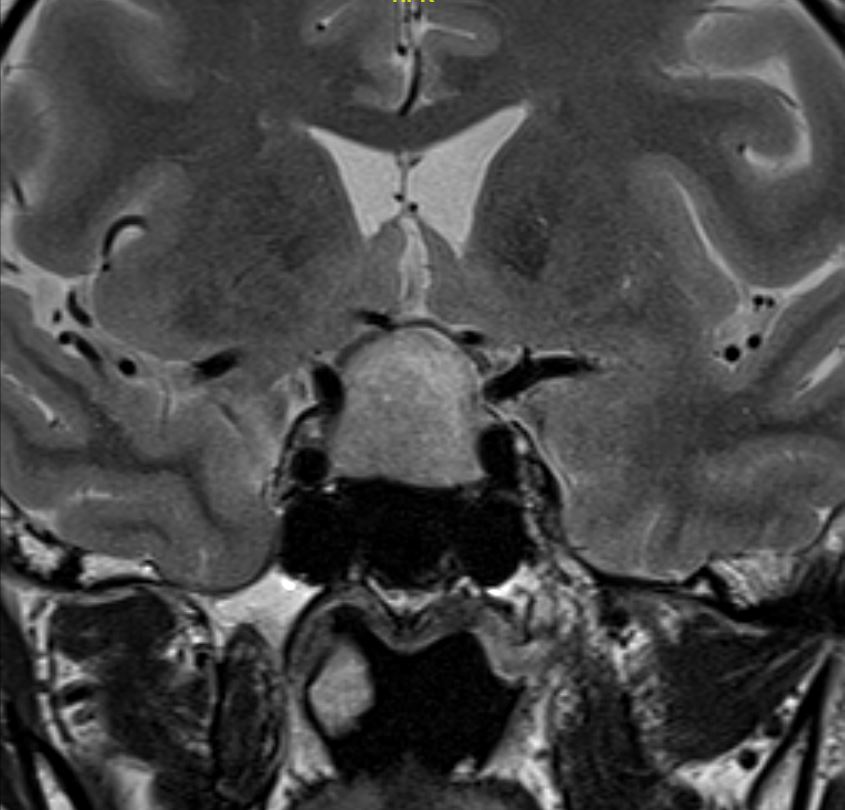

患者为63岁患者,因头痛伴有视物模糊2个月前来就诊,检查头颅MRI检查发现鞍区占位性病变,肿瘤大小2.3cm,向上生长压迫视交叉,两侧侵犯海绵窦。

T2WI